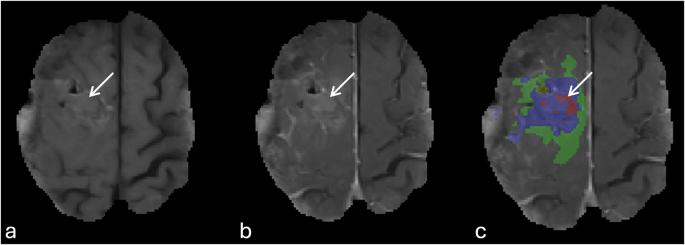

Oversampling of peritumoral non-enhancing T2/FLAIR hyperintensities (Fig. 7a,d).

Fig. 7 Errors of automatic tumor segmentation related to T2 and FLAIR signal abnormalities. (a, and d) image show the oversampling of FLAIR hyperintensities surrounding the tumor (arrows). (b, and e) images show incomplete delineation of FLAIR hyperintensities particularly in the contralateral occipital lobe (arrows). (c, and f) images represent misidentification of ventricular zone (occipital horn of the left lateral ventricle, arrows) adjacent to the tumor an assigning it as part of the resection cavity (yellow).

Incomplete delineation and under sampling of the non-enhancing T2/FLAIR hyperintensities surrounding the tumor and missing infiltrative component particularly crossing the midline into contralateral cerebral hemisphere (Fig. 7b,e)

Incorrect segmentation and improper assignment of ventricular regions adjacent to the tumor as non-enhancing tumor or resection cavity (Fig. 7c,f).